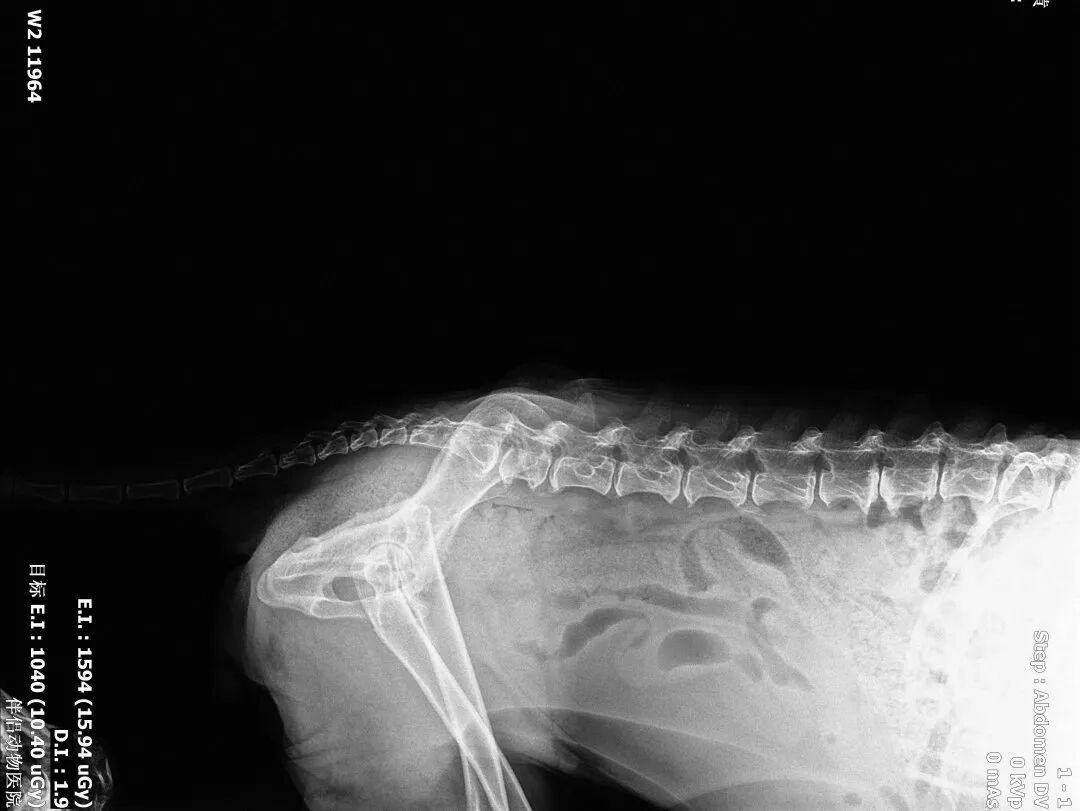

该犬长期在外流浪,后肢无法站立,触诊有疼痛感,经拍片诊断后发现有股骨头脱出的情况。

2、血常规、生化、凝血、DR(正侧)

术后正位片

术后侧位片